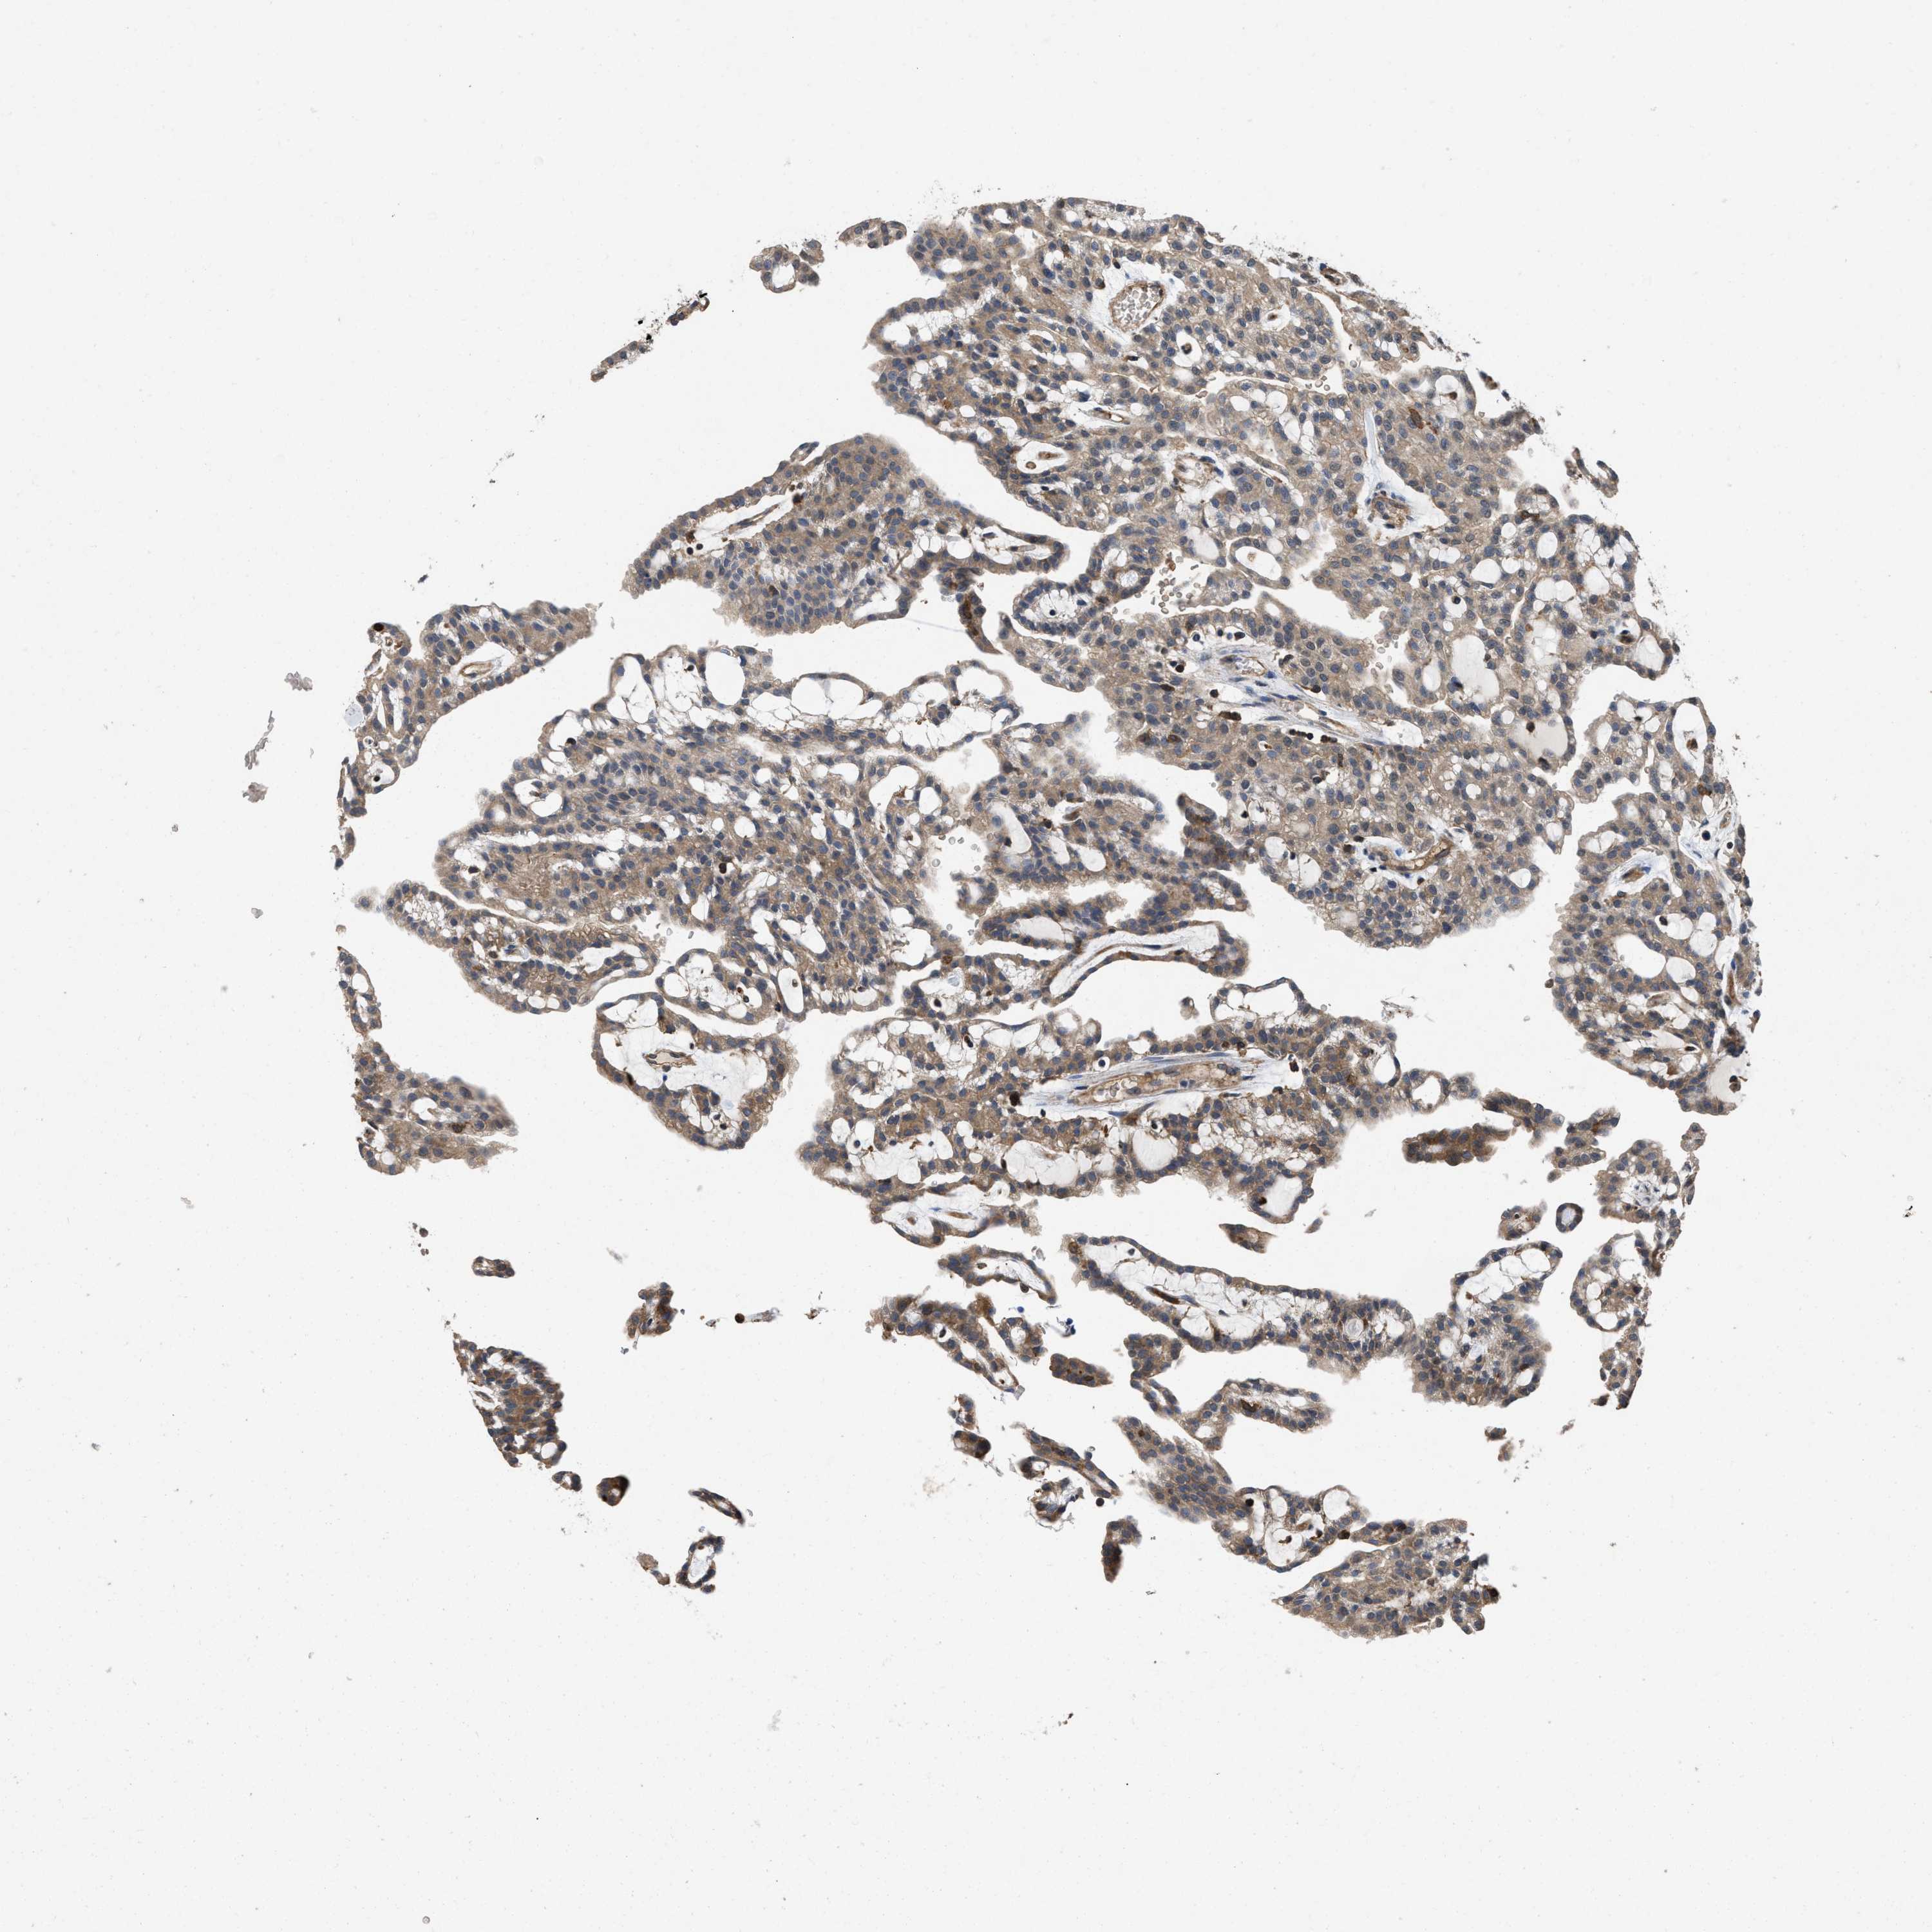

CANCER RENAL CANCER Show tissue menu

KICH TCGA KIRC TCGA KIRC VALIDATION KIRP TCGA PROTEIN RCC CPTAC PROTEIN EXPRESSION